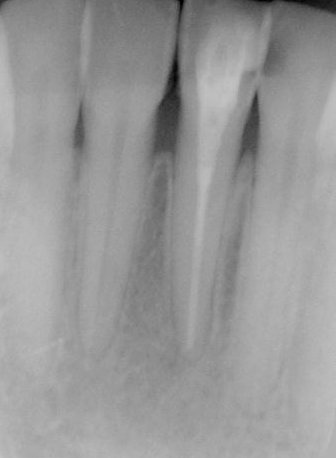

図1c 歯根端切除および 嚢胞摘出後のレントゲン写真